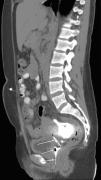

A 24 year old female patient was diagnosed with end stage renal disease during pregnancy. There was no other etiological factor, but hypertension. Patient was recommended 20hours of hemodialysis, but she refused and gave birth to a living child on the 38th gestational week. She has been on CAPD for the last 3 months. Since last week she has started to have abdominal pain accompanied with nausea and fever (>38°C). With these complaints she was referred to our policlinic and her peritoneal fluid cell count was found 4860/mm3 (95% polymorphonuclear leukocytes). Cultures were obtained and she was admitted to our hospital with the diagnosis of peritonitis. Blood analysis showed leucocytes 9000/mm3, hemoglobin: 8.8g/dl (11.5–16), C-reactive protein: 14.2mg/dl (0–0.5), sedimentation: 135mm/hour. Pseudomonas aeruginosa was detected in blood cultures. She was on empiric ceftazidime and cefazolin treatment and treatment was continued because P. aeruginosa was found sensitive to this treatment. Urine culture remained sterile. Patient stated that there is dialysate in her vagina. She was consulted with obstetrics and gynecology regarding any fistulas. A urine catheter was placed and it is understood that origin of dialysate was vagina. Contrast enhanced computerized tomography was done showing a vaginal fistula (Figs. 1 and 2). CAPD catheter was removed. Surgical operation was found unnecessary and hemodialysis was started. Patient was discharged after 3 weeks of ant biotherapy.

Patients on CAPD have an increased risk of both hernia formation and dialysate leakage as an intraperitoneal pressure related complications. One of the rare peritoneal fluid leakage is through processus vaginalis3 and main mechanisms include leakage through the fallopian tube and then the uterus and vagina, or leakage through a fistula between the uterus and the peritoneal cavity formed after surgery.3 One of the reason for fistula formation is peritonitis which is often caused by skin bacteria penetration via transvisceral, transvaginal or hematogenous spread of organisms, and the CAPD catheter can become colonized by bacteria creating a biofilm that repeatedly seeds the peritoneum.4

In our case, a rare entity; vaginal fistula and also another rarely seen clinic; peritonitis secondary to vaginal fluid were present. Probably secondary to the fistula, peritonitis developed and after peritonitis, fluid from fistula tract has increased and caused vaginal leakage.